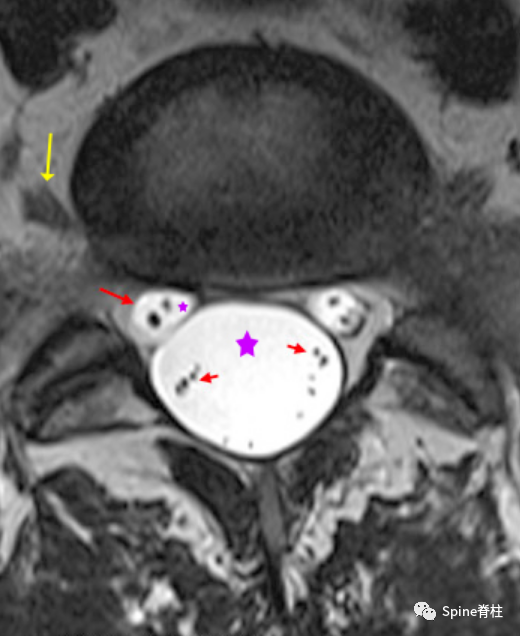

腰椎MRI的L5-S1椎间盘横断面。黄色箭头为L5神经根。可见巨大圆形的硬膜囊,充满脑脊液(大紫星和极亮的白色)。在2点和10点,可见S1走行根(左侧大红色箭头),其中也充满脑脊液(小紫星),也可看到S1走行根的感觉神经根和运动神经根。这三个圆形结构(硬膜囊和两个走行根)共同构成了“米老鼠”外观,典型通常仅在L5-S1水平,有时在L4-5水平也可见。

与上图为同一图,并做了进一步的标记